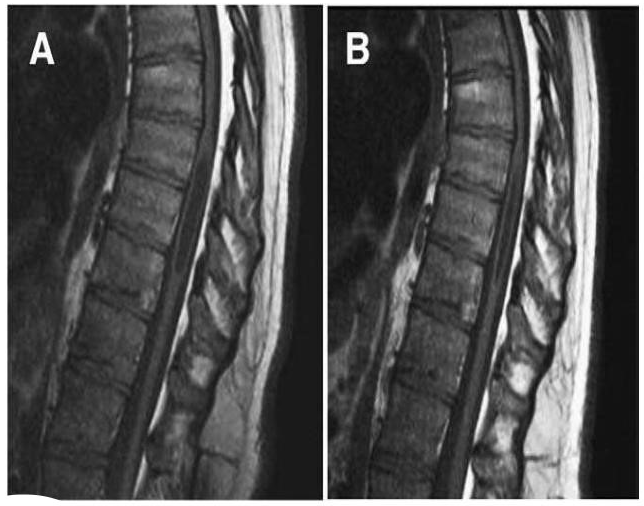

Fig.2 Valutazioni morfometriche riguardanti la CCJ in una donna di 24 anni con CM-I/TCS prima e dopo un fallito intervento della Chiari. A: Una immagine preoperatoria di MR medio sagittale pesata in T1, mostra un allungamento del tronco encefalico (BSL =68,2 mm), dislocamento verso il basso del midollo (MH = 12,9 mm), lo spostamento verso il basso del cervelletto (4VH = 7,6 mm) ed erniazione delle tonsille cerebellari (TH = 17,8 mm). Per ridefinire la linea M su radiografie postoperatorie, la distanza tra la protuberanza interna occipitale e la linea M è stata misurata tracciando una linea perpendicolarmente alla linea T (linea tratteggiata). B: La scansione postoperatoria con la linea M ridefinita, 6 mesi dopo la decompressione della fossa posteriore mostra ptosi cerebellare con maggiore allungamento del tronco encefalico (BSL = 72,7 mm), maggiore spostamento verso il basso del midollo (MH = 7,6 mm), maggiore dislocamento verso il basso del cervelletto (4VH = 12,9 mm) e maggiore erniazione delle tonsille cerebellari (TH = 25,0 mm). L’asterisco indica il tubercolo gracile.

I rapporti morfometrici delle strutture ossee e neurali a livello delle TLJ e CCJ sono riportati nella tabella 4. Negli individui sani del campione di controllo, la localizzazione del CMD, misurata come la distanza tra la lamina superiore L1 e la punta del CMD (vedi figura 1A), si è spostata rostralmente con progressione aritmetica durante la crescita e lo sviluppo, da una media di 28.2 mm ± 8.9 SD, in un’età compresa tra gli 0 ed i 3 anni, fino ad una media di 21.2 ± 11.8 SD in età matura. Non ci sono state differenze significative nella posizione del CMD nei pazienti con CM-I/TCS, LLCT/TCS e gli individui sani del campione di controllo dopo gli 8 anni d’età, sebbene le misure avessero ampie SDs, comuni alle curve di distribuzione normale [60]. Nei pazienti di età compresa fra 0 e 7 anni, la posizione della CMD era bassa rispetto a quella degli individui sani del campione di controllo (in media, 28.3 e 23.1 mm, P < .01). Si è potuto identificare, con sicurezza, il FT con immagini di MR solamente in 9 bambini (12%) e 20 adulti (9%). La BSL, misurata come la distanza tra la giunzione pontomesencefalica ed il margina postero-inferiore del tubercolo gracile, era maggiore nei pazienti con CM-I/TCS e LLCT/TCS rispetto agli individui sani del campione di controllo, in tutte le fasce d’età (in media, 8.3 mm, P < .001). Il valore dell’allungamento del tronco encefalico è stato maggiore nei bambini rispetto agli adulti (in media, 10.1 e 5.5 mm, P < .001). Abbiamo escluso le valutazioni effettuate su 9 dei 74 bambini (12%) e su 35 dei 244 adulti (14%), nei quali il margine inferiore del tubercolo gracile poteva non essere identificato con sicurezza. Non vi erano significative differenze nel grado di erniazione tonsillare nei bambini e negli adulti. L’MH era ridotta, in media, di 4.6 mm (P < .001) e la distanza del quarto ventricolo al di sotto della linea di Twining, era incrementata in media di 4.2 mm (P < .001), rispetto agli individui sani del campione di controllo. L’accorciamento di MH e l’incremento della distanza del quarto ventricolo al di sotto della linea di Twining, venivano considerate come prova dello spostamento verso il basso del romboencefalo senza che vi fossa clivus corto ed un corto sovraoccipite. Queste anomalie tendevano ad essere pronunciate in pazienti che sviluppavano ptosi cerebellare dopo l’intervento di decompressione della Chiari (Fig.2B).